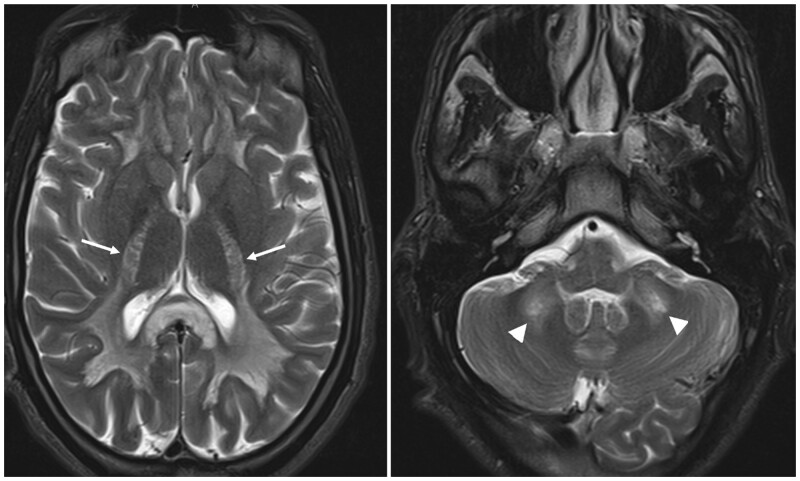

Heroin-induced leukoencephalopathy (HLE) is a rare toxic encephalopathy associated primarily with heroin inhalation, commonly referred to as "chasing the dragon." This study presents a clinical case of a 27-year-old polydrug user diagnosed with HLE during hospitalization for rapidly progressive flaccid tetraplegia and aphasia. The clinical manifestations encompassed cerebellar and bulbar dysfunction, coupled with motor impairment and altered consciousness. Based on the clinical data and MRI results, HLE was identified as the most likely cause. This article aims to provide insights into the clinical and radiological aspects of HLE, emphasizing the diagnostic significance of radiological findings. The gold standard examination for diagnosis is MRI, crucial due to the difficulties in obtaining histological confirmation for this rare condition.